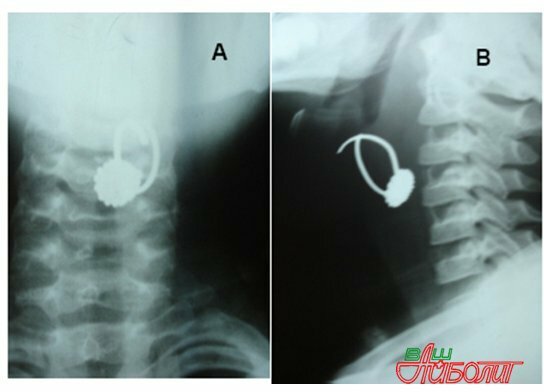

Для того чтобы диагностировать наличие инородного тела в бронхах, применяются такие вспомогательные методы, как рентгенологический: в него включены рентгеноскопия и рентгенография органов, расположенных в области грудной клетки.

При любом подозрении инородного тела в бронхах, родителям рекомендуется обратиться к специалисту, который проведет рентгенографию органов, расположенных в области грудной клетки, как правило, это позволяет обнаружить как сам предмет, так и наличие ателектаза, вентильного вздутия легких.